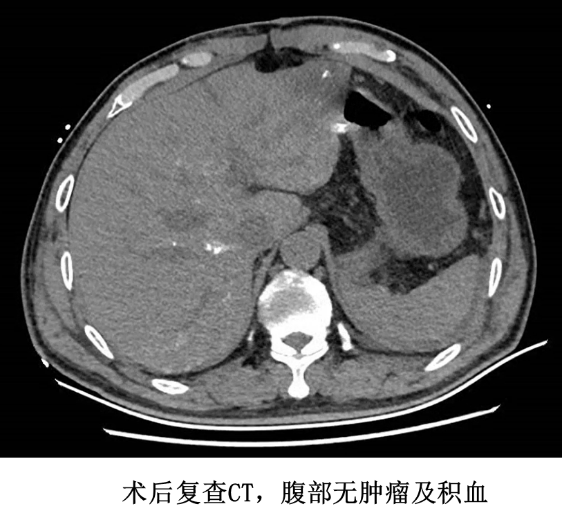

考虑到患者经历失血性休克打击,术后需呼吸机支持,患者被转入 ICU 病房继续治疗。术后通过呼吸支持、输血、护肝、补液、营养支持、控制血糖等治疗后,患者血红蛋白稳步上升,呼吸功能逐步好转,并逐步恢复饮食及活动。腹腔引流管已拔除,切口愈合良好并拆线,术后 9 天顺利出院。